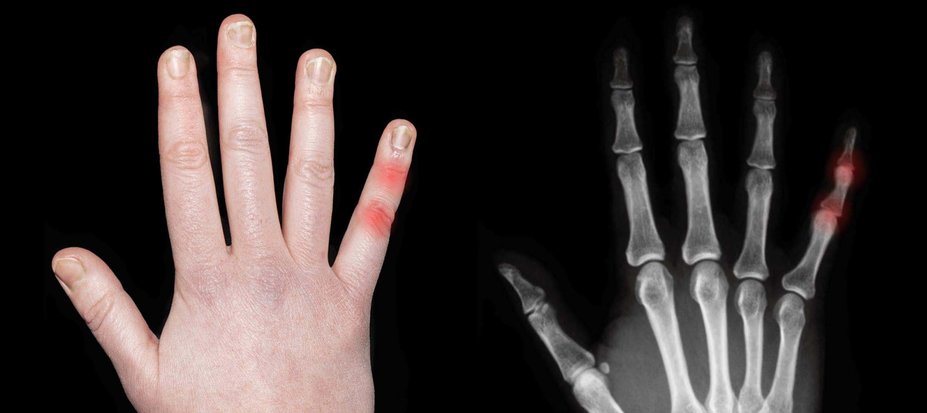

Screening and treating patients with PsO for PsA can help stop further irreversible joint damage.

When your patients with PsO develop PsA, their joints are in danger1

Artist’s representation of early radiographic damage.

One study revealed PsA can cause irreversible joint damage in as little as 6 months from symptom onset.6

Another study found that ~1 in 4 patients with early PsA had at least 1 erosion.7†